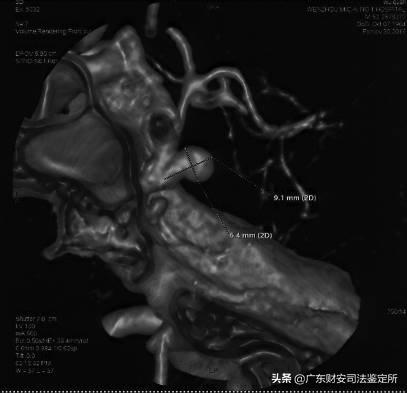

2016年11月30日 CT*片A**:左侧颈内动脉后交通端见一瘤样突出,表面光滑,瘤体向后外侧,大小约6×9mm,瘤颈较窄,余无殊。提示左侧颈内动脉后交通端动脉瘤。

复阅被鉴定人2016年11月30日(伤后8天) CT*片A**示左侧颈内动脉后交通端动脉瘤,瘤体向后外侧,大小约6×9mm,瘤颈较窄;于2016年12月2日(伤后10天)行经皮颅内动脉成形术,术中所见亦证实左侧颈内动脉C3段动脉瘤,约6.2×9.0mm,瘤颈4.7mm。根据上述造影检查及术中所见,被鉴定人左侧颈内动脉瘤形成,属于中型囊状动脉瘤,此类动脉瘤的主要病因为管壁的先天薄弱。

(图3,2016年11月30日CT*片A**,左侧颈内动脉后交通端动脉瘤,瘤体向后外侧,大小约6×9mm,瘤颈较窄)